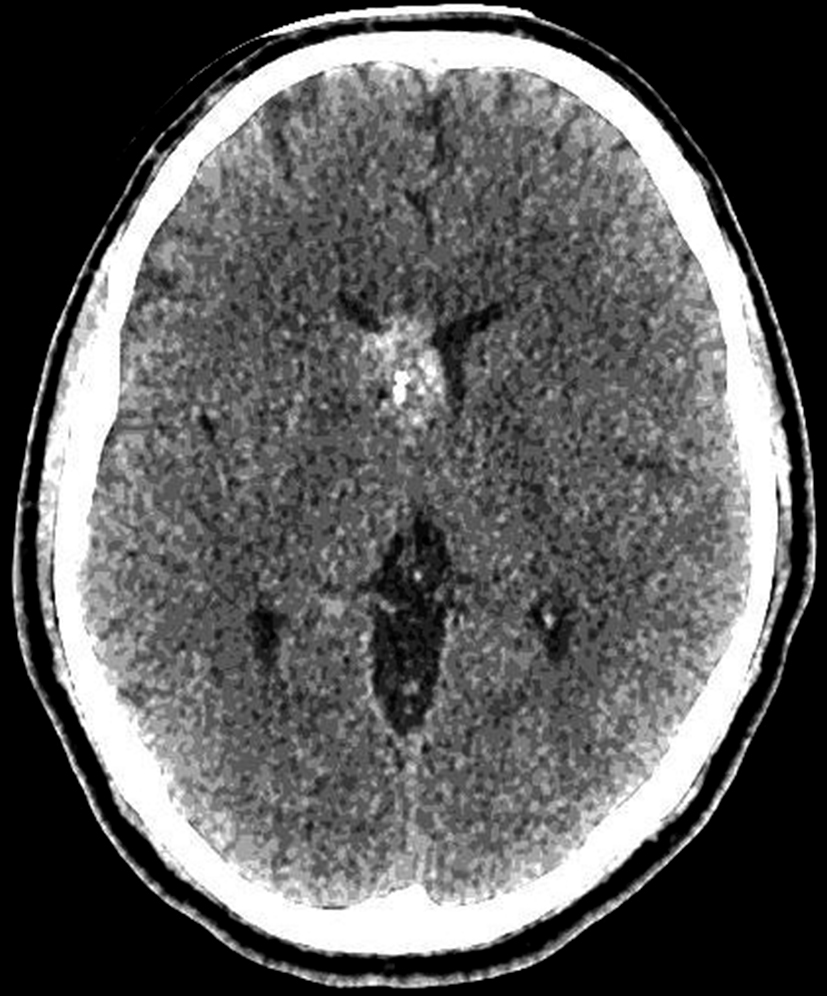

Se presenta el caso clínico de un paciente de sexo masculino, de 36 años de edad, sin antecedentes personales a destacar. Consulta por cefalea holocraneana de larga data, sin déficit neurológico y examen físico normal. Dada la clínica del paciente se realiza una tomografía computada de cráneo sin contraste intravenoso que identifica una lesión bien definida espontáneamente hiperdensa, heterogénea con calcificaciones puntiformes localizada en el asta frontal del ventrículo lateral derecho. No hay edema peri-lesional, efecto de masa ni hidrocefalia (Figura 1- A). Debido a los hallazgos se decide administrar contraste intravenoso, no evidenciándose realce significativo de la lesión (Figura 1- B).

a) TC sin contraste. Lesión intraventricular hiperdensa, heterogénea con pequeñas calcificaciones.

a) TC con contraste. No se identifica realce significativo de la lesión.

En la TC sin contraste, el cavernoma es una lesión bien definida e hiperdensa. El aumento de la densidad puede tener un aspecto punteado, que puede representar calcio, sangre o una combinación de ambos y el realce tras la administración de contraste varía de ninguno a muy intenso (1,3,5).